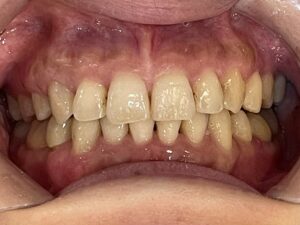

▼治療後(After)

約15か月の矯正で歯列はきれいに整い、ガタガタが解消されました。

見た目の印象が大きく変化し、患者さまも大変満足されていました。